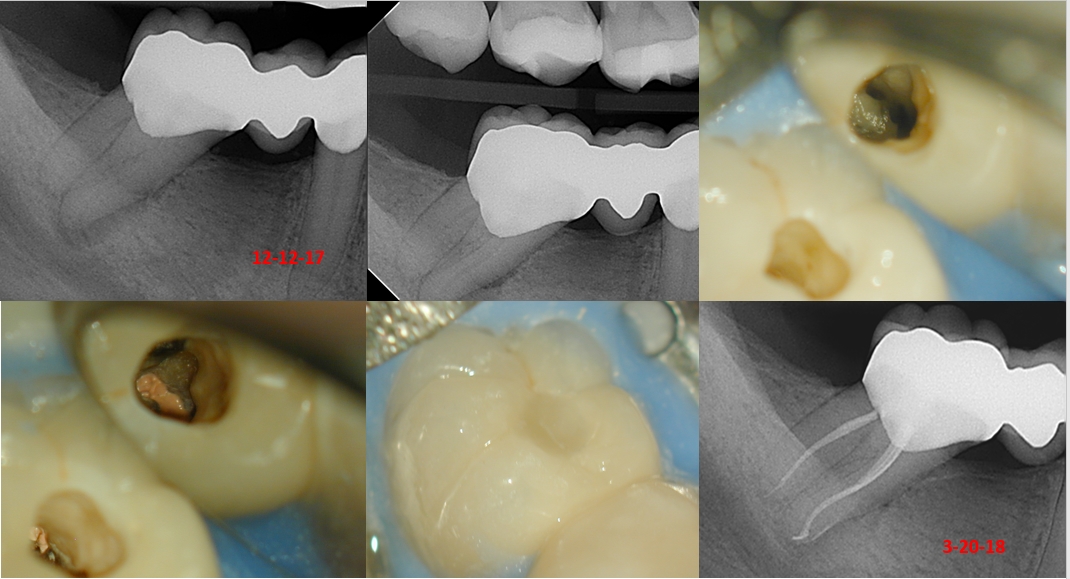

Case II–Here is another necrotic case with a PAL, and symptomatic. The case was initiated in December of 17, and completed three months later, with an interim CH change. Patient was asymptomatic by the second appointment. I obturated with I saw sufficient osseous healing. The access is “somewhat minimal given the angulation of the tooth and the amount of opening the patient could tolerate. However, the canal final shapes are, again, 17/.04 VTapers.